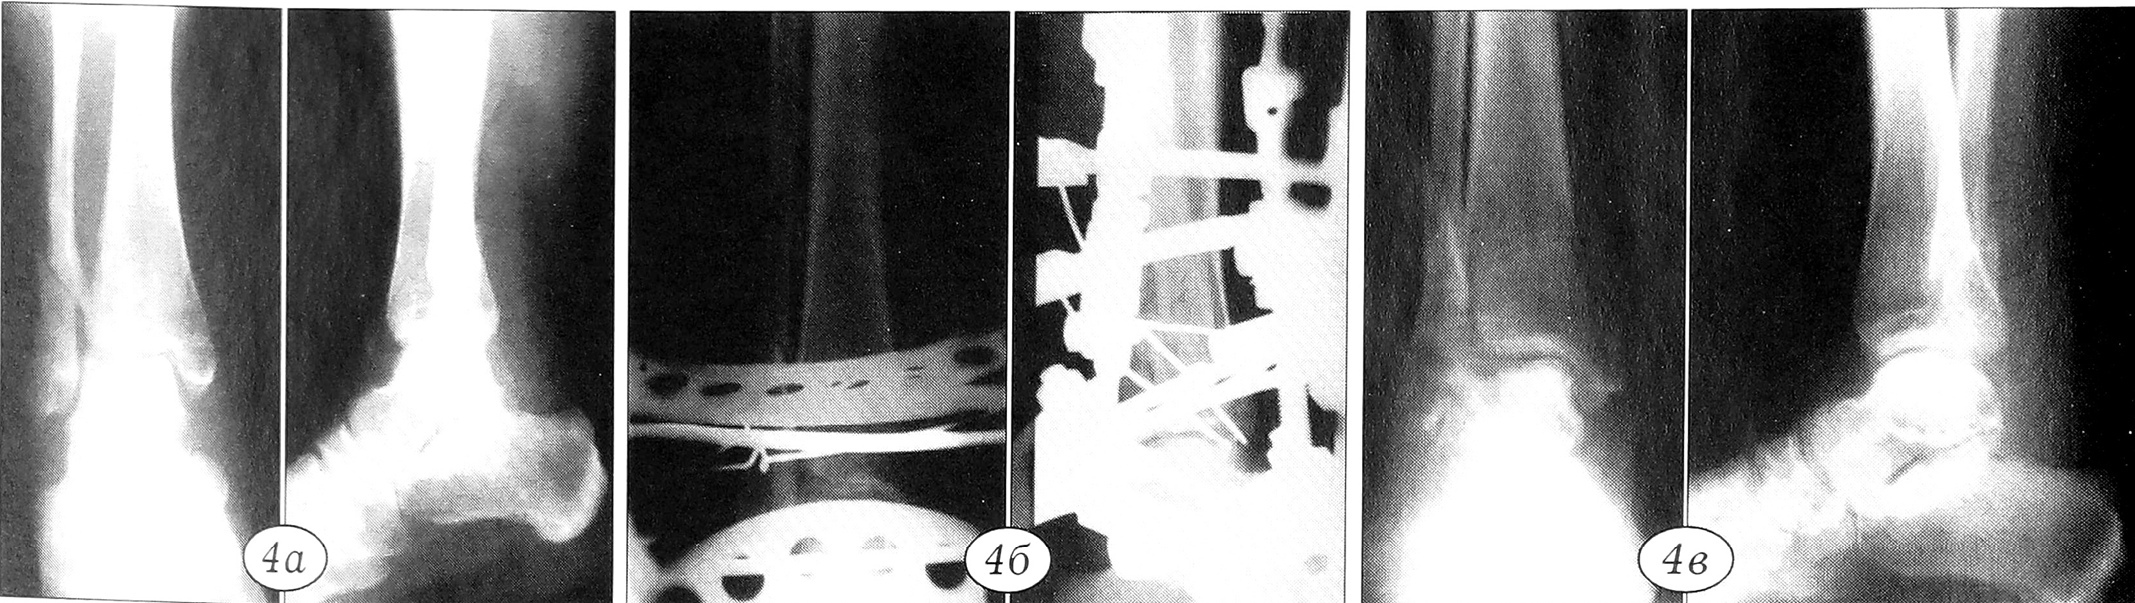

Больная М .. 37 лет, поступила в ЦИТО по поводу перелома наружной лодыжки, разрыва дистального межберцового синдесмоза, разрыва дельтовидной связки, подвывиха стопы кнаружи 4-недельной давности (рис. 4, а).

При поступлении жалобы на отсутствие опорности правой нижней конечности. Движения в правом голеностопном суставе резко ограничены и болезненны. Область голеностопного сустава деформирована, отечна. Через 38 дней после травмы под перидуральной анестезией произведена репозиция отломков с использованием аппарата для репозиции, отломки малоберцовой кости ориентированы в проекции одноименной вырезки большеберцовой кости, на суставные концы голеностопного сустава наложен шарнирнодистракционный аппарат. Произведено вправление подвывиха стопы, устранение диастаза межберцового синдесмоза (рис. 4, б). Фиксация в аппарате продолжалась 2,5 мес, была произведена разработка движений в аппарате, после чего он снят. При осмотре через 4 мес: движения в голеностопном суставе 110-80°, безболезненные, опорность конечности восстановлена, больная работает по специальности (рис. 4, в).

Рис. 4. Рентгенограммы больной М.